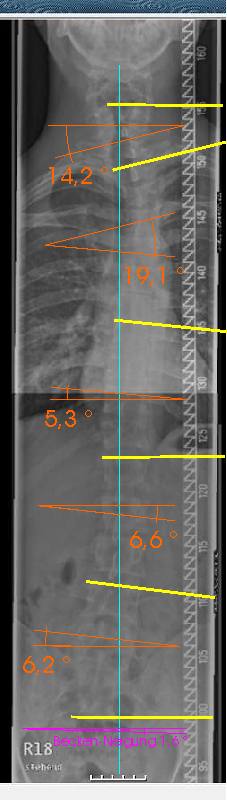

- LWS+BWS stehend.jpg

- Lenden+Brustwirbelsäule

- (26.27 KiB) 557-mal heruntergeladen

- orange = Winkel der gelben Linien

Zuerst mal zu dem RöBi. Für mich sieht es so aus, als ob schon das Becken schief steht und die WS nicht gerade steht. Eigentlich sind im unteren Bereich nur mehrere sehr kleine, sich z.T. gegenseitig aufhebende Krümmungen zu erkennen. Durch den Schiefstand in der Beckenregion kommt die WS bis zur oberen BWS aus dem Lot, was durch eine mäßige (Gegen-) Krümmung von ca. 19° nur unvollständig ausgeglichen wird. Die Krümmung der oberen BWS wird wiederum durch eine Krümmung im BWS-HWS-Übergang kompensiert.